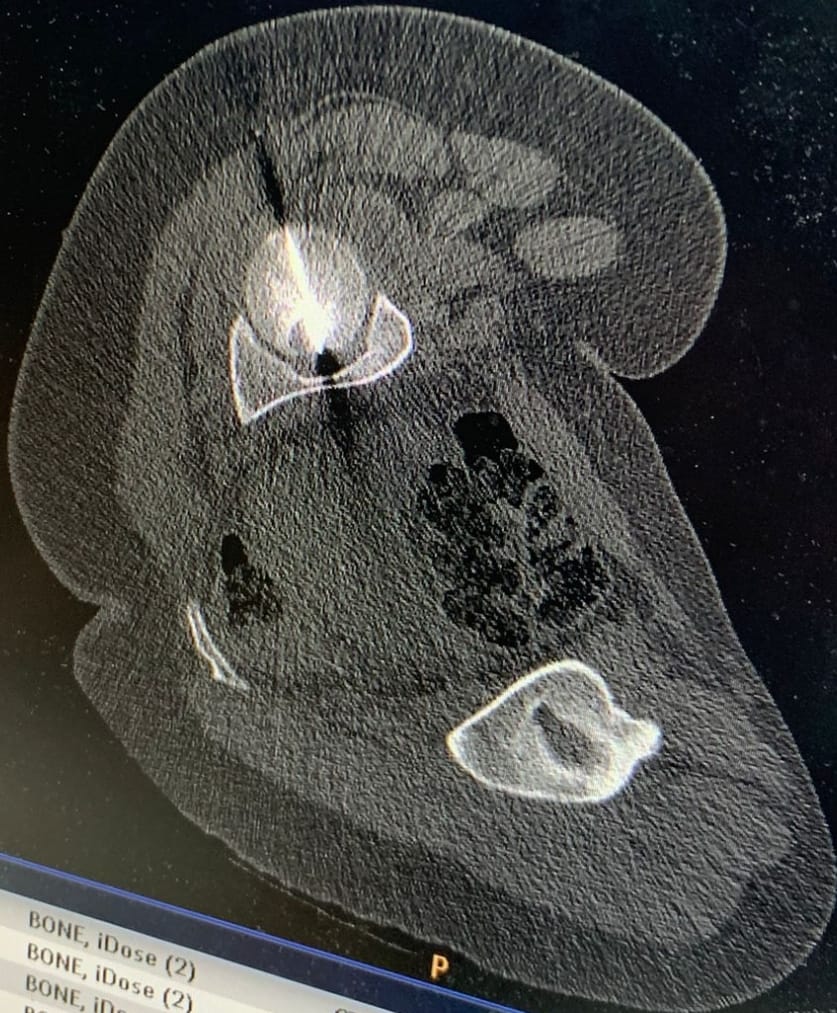

أجرى مستشفى الجامعة الأردنيّة، مؤخّرًا، تدخلًا علاجيًّا متقدّمًا في قسم الأشعة، استطاع من خلاله فريقٌ طبيٌّ متعدد الاختصاصات معالجة ورمٍ عظميّ في موقعٍ شديد الحساسيّة داخل رأس عظم الفخذ لمريضٍ ثلاثينيّ، ويُعد هذا الموقع من أكثر المواضع صعوبةً في الوصول إليها جراحيًّا، ما يجعل الخيارات التقليديّة محدودة ويزيد من تعقيد التعامل مع الحالة، لاسيما وأنّ المريض كان يُعاني من آلام حادّة أثّرت بشكل كبير على قدرته على الحركة وممارسة أنشطته اليوميّة.

وبيّن البطوش، أنّ الفريق الطبي نجح في الوصول إلى مركز الورم بدقة عالية باستخدام تقنيّة التصوير الطبقيّ المحوريّ (CT Scan)، تلا ذلك إجراء الكي بالتقنيّة الحراريّة باستخدام المايكروويف (Microwave Ablation)، وهي من أحدث التقنيّات العالميّة في علاج أورام العظام دون الحاجة إلى التدخّل الجراحيّ المفتوح.